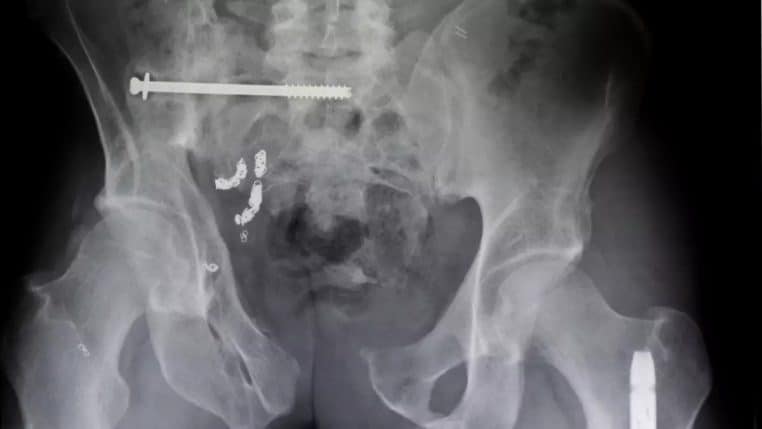

Vous seriez étonné de la diversité des cas recensés ! En effet, les bases médicales regorgent d’exemples surprenants. Shampooings, lampes, lunettes ou même jouets pour chiens ont été retrouvés dans le rectum. Defector a compilé une liste des 25 objets les plus improbables. Ainsi, l’imagination des patients dépasse souvent la logique médicale.

La liste compilée par la U.S. Consumer Product Safety Commission inclut des objets aussi variés ! Notamment des vis, des clous, des tondeuses à barbe emballées, un bâton, ou une poire à dinde. À cela s’ajoute un cure-dent dentaire et un bouchon de vin coincé dans le rectum des patients.

On y a retrouvé également : un porte-maïs, un surligneur, une baguette magique, des billes, une boîte de film, une sandale, une poignée de porte, une ampoule, une lampe torche, un stylo vape, deux crayons, une pipe en forme de maïs, des pâtes crues, un morceau de tondeuse à poils du nez, une paire de lunettes, un œuf et même un étui rectangulaire de brosse à dents de voyage.